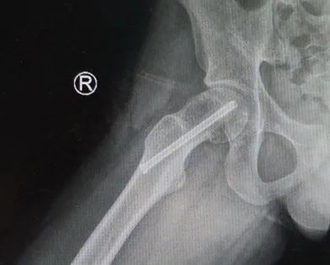

病例2 男,14岁,右侧重度SCFE,行闭合复位,经皮空心钉固定术

病例2 术中股骨头骺内实时血供监测显示复位后,股骨头血供良好

病例2 术后17个月复查,X线示位置良好,无股骨头缺血坏死发生